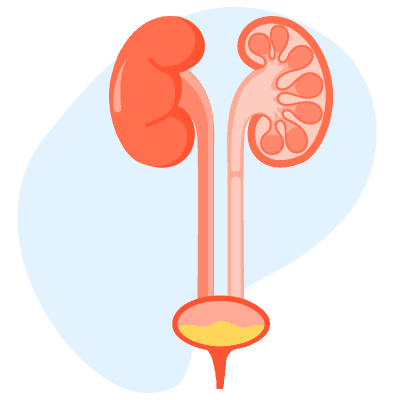

အဓိပ္ပါယ်ဖွင့်ဆိုချက်Bladder Cancer (ဆီးအိမ်ကင်ဆာ) ကဘာလဲ။ ဆီးအိမ်ကင်ဆာဆိုသည်မှာဆီးများကိုသိုလှောင်သောတင်ပဆုံနေရာရှိ ပူဖေါင်းပုံဆီးအိမ် တွင် ဖြစ်ပွားသောကင်ဆာတစ်မျိုး ဖြစ်ပါသည်။ ဆီးအိမ်ကင်ဆာသည် ဆီးအိမ်အတွင်းနံရံကိုကာထားသောဆဲလ်များတွင် စတင်ဖြစ်ပွားလေ့ရှိပါသည်။ ဆီးအိမ်ကင်ဆာအများစုသည် ကုသ၍လွယ်သောအစောပိုင်းအဆင့်တွင် ရောဂါ အဖြေရှာသိရှိနိုင်ပါသည်။ သို့သော် အစောပိုင်းအဆင့်ဆီးအိမ် ကင်ဆာသည်လည်းထပ်မံဖြစ်ပွားနိုင်ပါသည်။ ထို့ကြောင့် ဆီးအိမ် ကင်ဆာပျောက်ကင်းသူမျာသည် နောက်ဆက်တွဲ စစ်ဆေးမှုများကိုရောဂါပျောက်ပြီး နှစ်အနည်းငယ် ကြာသည် အထိ ပြုလုပ်ရန် လိုအပ်ပါသည်။ Bladder Cancer (ဆီးအိမ်ကင်ဆာ) က ဘယ်လောက်အဖြစ်များသလဲ ဆီးအိမ်ကင်ဆာသည် မည်သည့်အသက်အရွယ်တွင်မဆို ဖြစ်ပွားနိုင်သော်လည်းအသက်ကြီးသောလူများတွင် ပိုဖြစ်ပွားတတ်ပါသည်။ အမျိုးသားကျန်းမာရေးအဖွဲ့အစည်းအရတစ်နှစ်တွင် အမျိုးသား ၄၅၀၀၀ နှင့် အမျိုးသမီး ၁၇၀၀၀ သည် ဤရောဂါ ဖြစ်ပွားပါသည်။ သို့သော်လည်း အန္တရာယ် ရှိသောအချက်များကိုလျော့ချခြင်းအားဖြင့် ရောဂါကိုထိန်းချုပ် နိုင်ပါသည်။ ပိုမိုသောအချက် အလက် များအတွက် ဆရာဝန်နှင့် တိုင်ပင်ပါ။ လက္ခဏာများBladder Cancer (ဆီးအိမ်ကင်ဆာ) ရဲ့လက္ခဏာတွေကဘာတွေလဲ ဆီးအိမ်ကင်ဆာဝေဒနာသည်များသည် […]